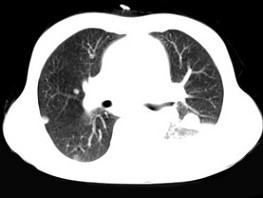

问题 女,55岁,胸痛伴咯血丝痰一周,胸部CT如图,最可能的诊断为 ( )

选项 A、多发性肺脓肿 B、结节病 C、左侧周围型肺癌并肺内转移 D、左侧中央型肺癌并肺内转移 E、转移性肺癌

答案 C